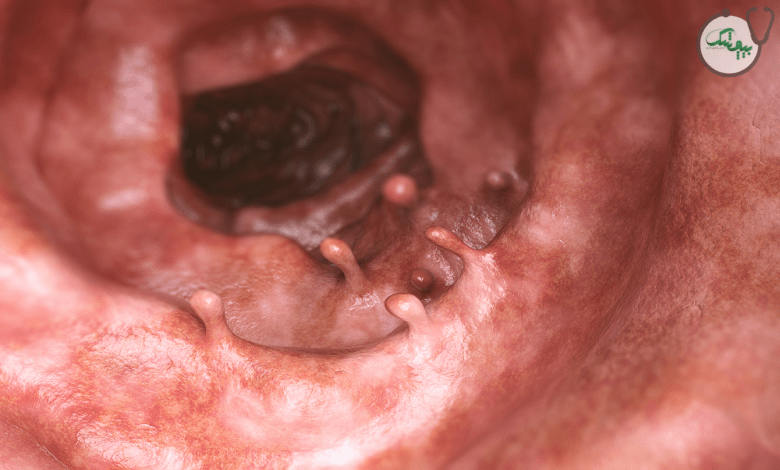

پولیپ های معده (پولیپ گاستریک)، توده‌ های کوچکی هستند که در پوشش داخلی معده ایجاد می‌ شوند. این پولیپ ها معمولاً به طور اتفاقی در طول آندوسکوپی تشخیص داده می شوند و در اغلب موارد خوش‌ خیم (غیرسرطانی) هستند، اما تعداد کمی از انواع آنها می‌ توانند به مرور زمان، پیش سرطانی یا سرطانی شوند.

زمانی که سلول های پوشش معده به طور غیر طبیعی رشد می کنند، ممکن است منجر به تشکیل توده های کوچکی شوند که به آنها پولیپ گفته می شوند. برخی افراد ممکن است فقط یک پولیپ داشته باشند و برخی دیگر ممکن است چندین پولیپ پراکنده در سراسر معده داشته باشند. تشخیص نوع پولیپ بسیار مهم است، زیرا نحوه مدیریت این بیماری را تعیین می کند.

تشخیص پولیپ معده

تشخیص پولیپ معده معمولاً در طول آندوسکوپی فوقانی انجام می‌ شود، که در آن یک دوربین انعطاف‌ پذیر وارد معده می شود و امکان مشاهده پوشش معده و هرگونه پولیپ در آن را فراهم می‌ کند. متخصصان، پولیپ‌ ها را بر اساس اندازه، تعداد، شکل و محل قرارگیری ارزیابی می‌ کنند. همچنین در صورت مشاهده پولیپ در طی آندوسکوپی، از بافت آنها نمونه برداری می شود تا نوع پولیپ و خوش خیم، پیش سرطانی یا بد خیم بودن آنها مشخص شود. در اغلب موارد برای تشخیص و ارزیابی پولیپ های معده تصویربرداری استفاده نمی شود، مگر اینکه پولیپ بسیار بزرگ باشد.